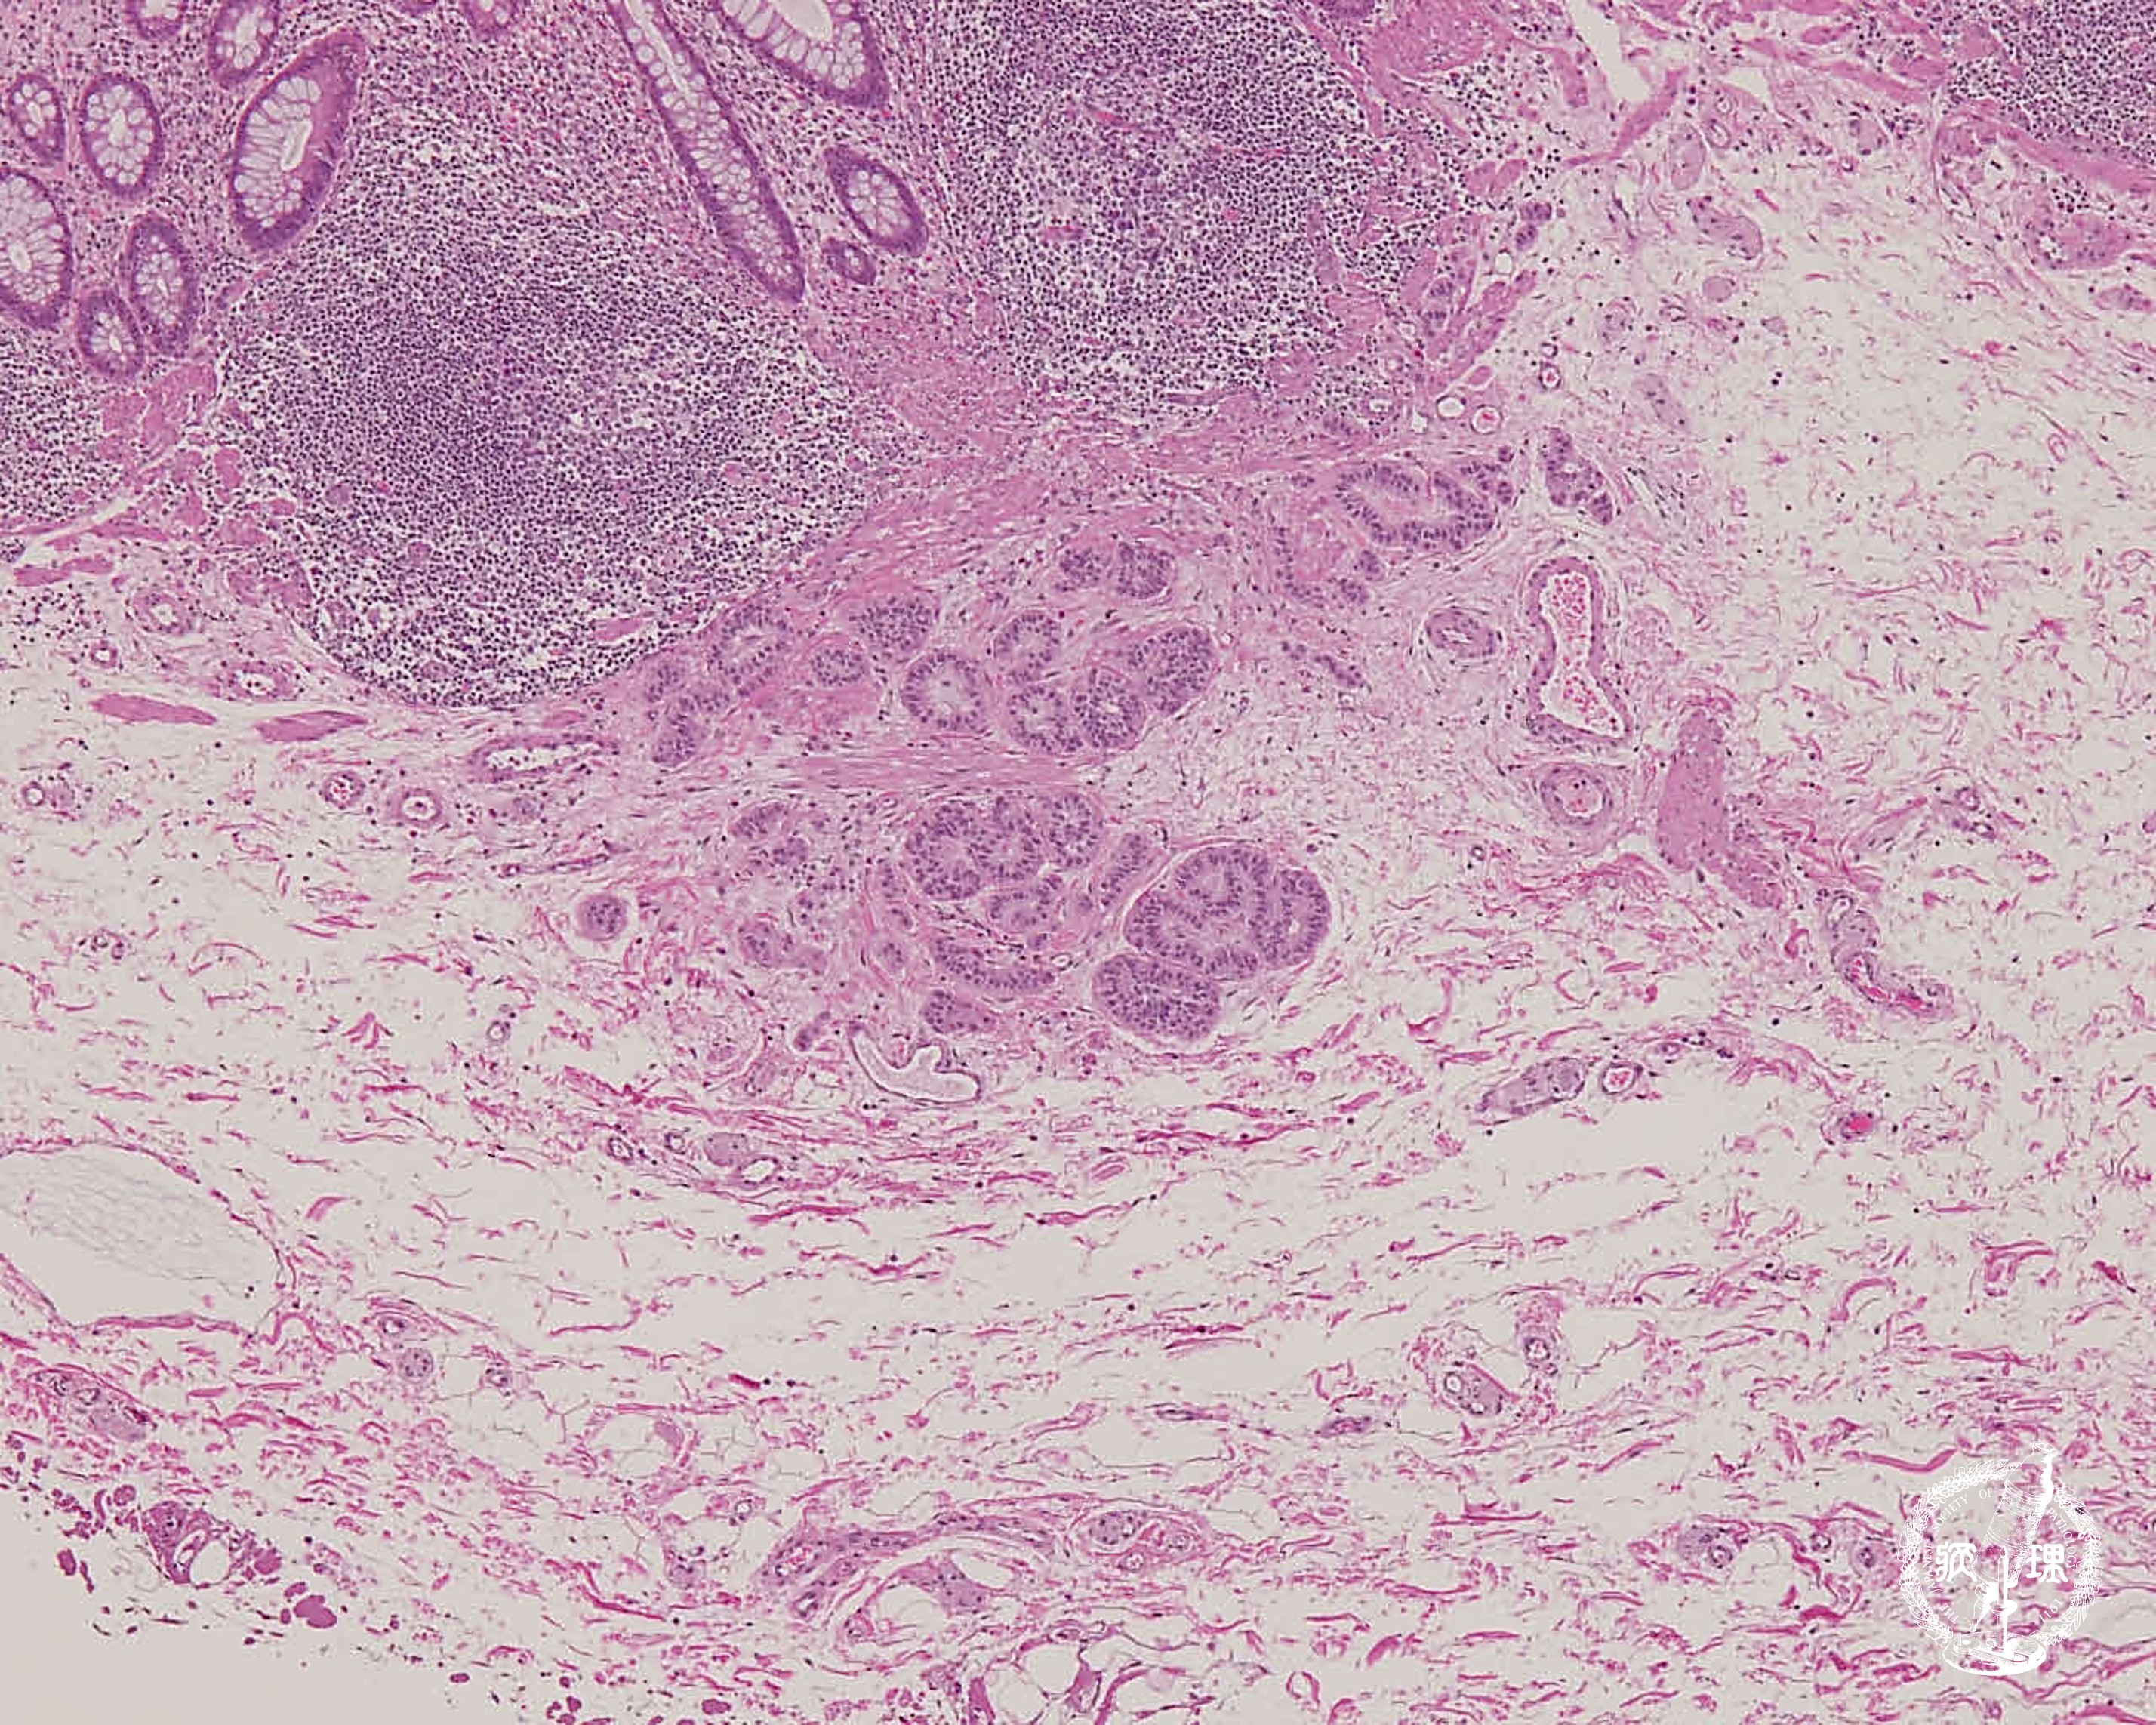

(10)大腸カルチノイド腫瘍

ミクロ像(HE弱拡大):直腸の粘膜下層に異型腺管の増生を認める(矢印)。